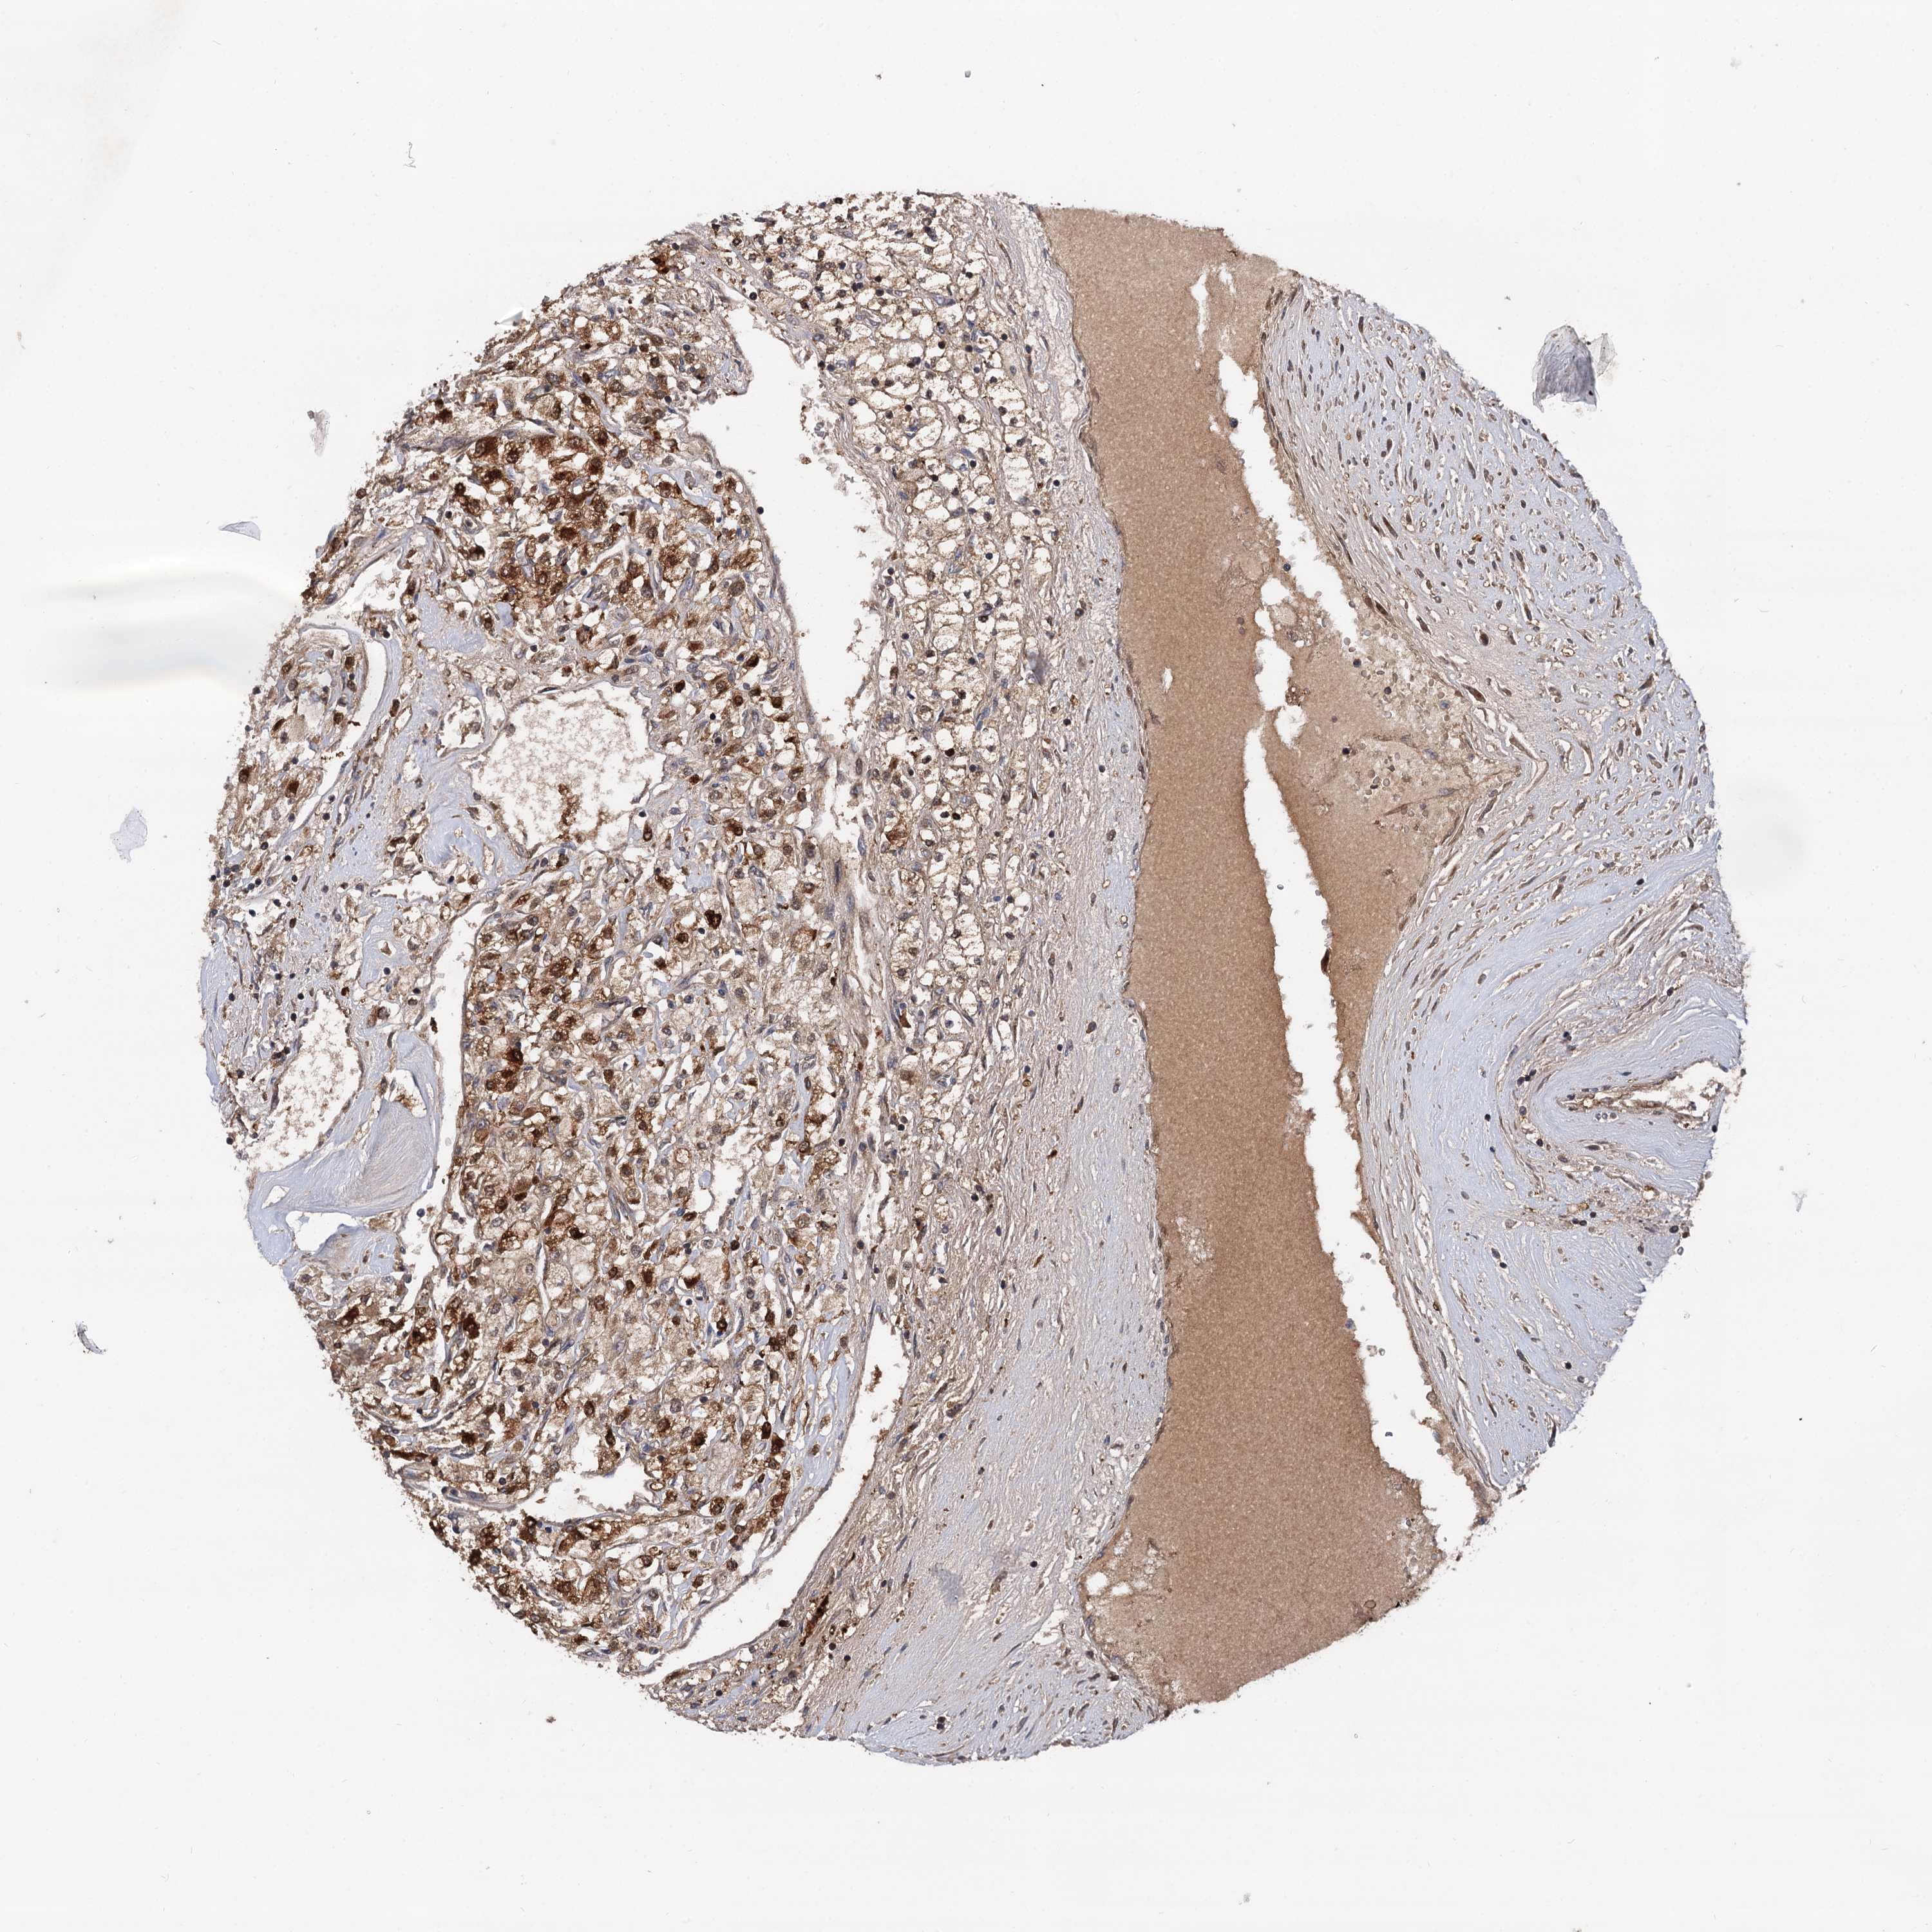

KIDNEY RENAL CLEAR CELL CARCINOMA (TCGA) - Interactive survival scatter ploti

The Survival Scatter plot shows the clinical status (i.e. dead or alive) for all individuals in the patient cohort, based on the same data that underlies the corresponding Kaplan-Meier plots. Patients that are alive at last time for follow-up are shown in blue and patients who have died during the study are shown in red.

The x-axis shows the expression levels (FPKM) of the investigated gene in the tumor tissue at the time of diagnosis. The y-axis shows the follow-up time after diagnosis (years). Both axes are complimented with kernel density curves demonstrating the data density over the axes. The top density plot shows the expression levels (FPKM) distribution among dead (red) and alive patients (blue). The right density plot shows the data density of the survived years of dead patients with high and low expression levels respectively, stratified using the cutoff indicated by the vertical dashed line through the Survival Scatter plot. This cutoff is automatically defined based on the FPKM cutoff that minimizes the p-score. The cutoff can be changed by dragging the vertical line or by entering a cutoff value in the square labeled "Current cut-off".

Under the Survival Scatter plot the p-score landscape (black curve; left axis) is shown together with dead median separation (red curve; right axis). Dead median separation is the difference in median mRNA expression between patients who have died with high and low expression, respectively. It is calculated as follows: median FPKM expression of dead patients with high expression - median FPKM expression of dead patients with low expression. This is intended to aid the user in visually exploring custom cutoffs and the associated p-scores and dead median separation.

Individual patient data is displayed and can be filtered by clicking on one or more of the category buttons on the top of the page. Categories describing expression level and patient information include: high, low, alive, dead, female, male and tumor stages. The scale of the x-axis can be toggled between linear and log-scale by clicking on the "x log" button. Mouse-over function shows TCGA ID, patient information and mRNA expression (FPKM) for each patient.

& Survival analysisi

Kaplan-Meier plots summarize results from analysis of correlation between mRNA expression level and patient survival. Patients were divided based on level of expression into one of the two groups "low" (under cut off) or "high" (over cut off). X-axis shows time for survival (years) and y-axis shows the probability of survival, where 1.0 corresponds to 100 percent.

SELENOP is validated prognostic, high expression is favorable in Kidney Renal Clear Cell Carcinoma (TCGA)

: 189.99

Average pTPM 430.8

Number of samples 521